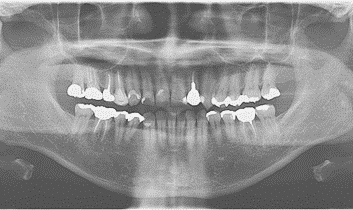

■パノラマエックス線撮影

口、顎全体を1枚の写真に写すエックス線撮影では、むし歯や歯周病、のう胞、腫瘍、唾石、骨折など歯と顎骨の中の病気や、上顎洞(副鼻腔)の炎症有無などを診ることができます。